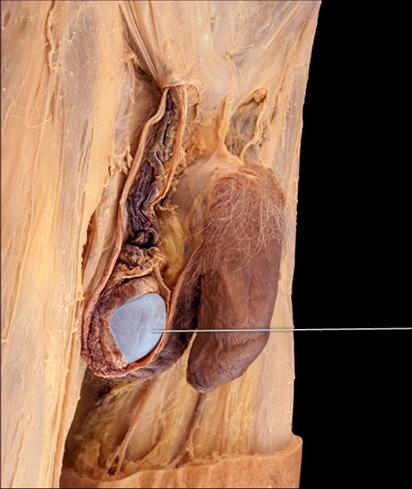

Identify the highlighted structure.

Corpus Cavernosum

Identify the highlighted structure.

Ductus Deferens

Identify the highlighted structure.

Epididymis

Identify the highlighted structure.

Glans Penis

Identify the highlighted structure.

Prostate

Identify the highlighted structure.

Penis

The highlighted structure (scrotum) contains a layer of smooth muscle that wrinkles the skin under cold conditions to help maintain the temperature of the testes. What is this muscle called?

Dartos

Identify the highlighted structure.

Spermatic Cord

The highlighted structure is surrounded by what erectile tissue?

Corpora Cavernosa

Identify the highlighted organ.

Testis